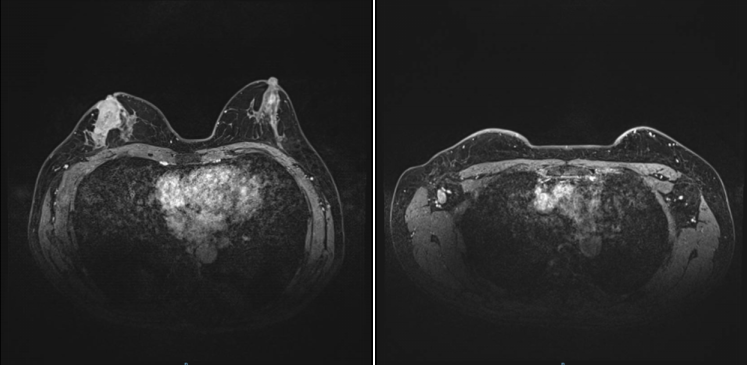

2021-11-30,钼靶:右乳外上象限较高密度肿块影,有浅分叶,约1.4×1.3cm大小,其内及邻近簇状分布细小多形钙化,符合乳腺癌诊断,BI-RADS 6类。右腋下见增大淋巴结影,约1.8cm直径大小。(图1)

图1.钼靶(2021-11-30)

图5.乳腺MR(2022-4-19)